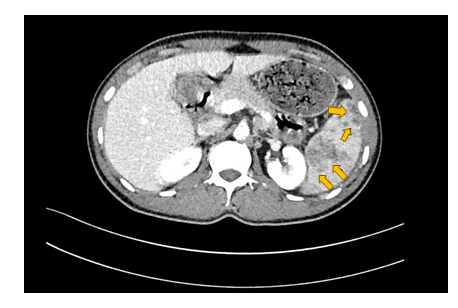

Later CT abdomen done showed multiple hypodense lesions of varying sizes are noted in the spleen; some of the lesions appear ill-defined and conglomerate. Multiple sub centimeter and borderline/mildly enlarged retroperitoneal lymph nodes were noted (Figure 1).

Figure 1 Contrast enhanced CT scan of the abdomen acquired in the Porto-venous phase showing multiple irregular ill-defined hypodense splenic lesions of varying sizes.